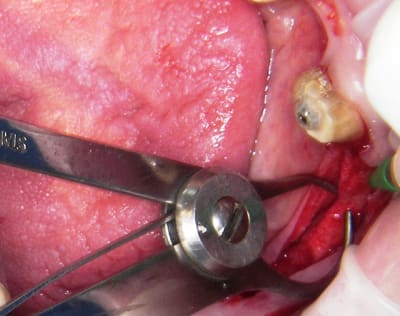

;Les photos:

1:

état initial,

disque diamanté

scie circulaire

4:

évolution

Tatum D1